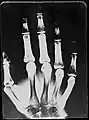

X-Ray image of right hand with no details in the bones at the bottom of the image

Original: X-Ray image of right Hand;